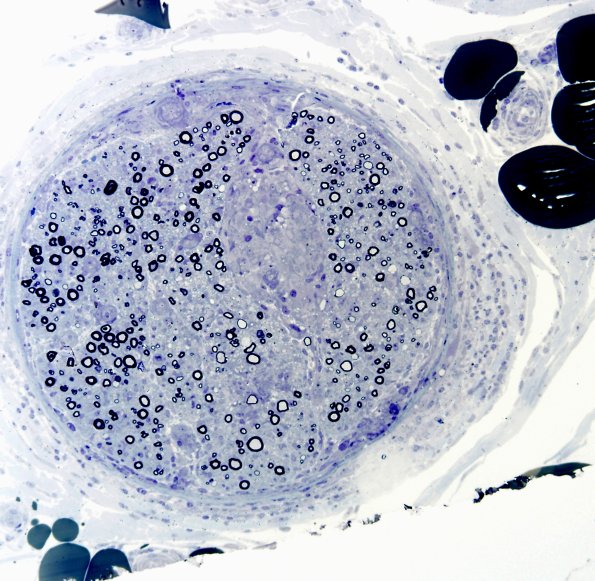

5B1-3 Plastic sections at successive increased magnifications show a fascicle with endoneurial granulomas. The axon loss and myelin thinning is more prominent in the margins of the granuloma. (Plastic sections)